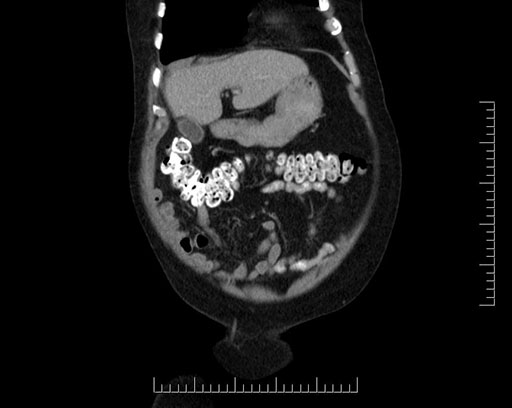

Whipple (pancreaticoduodenectomy) [case 7]

Coronal - stented